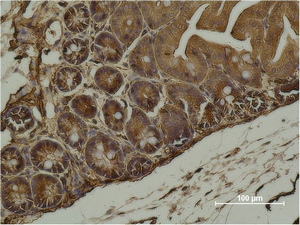

Immunohistochemistry analysis of paraffin-embedded mouse Cecal Tissue using alpha Smooth Muscle Actin antibody.High-pressure and temperature Sodium Citrate pH 6.0 was used for antigen retrieval. |